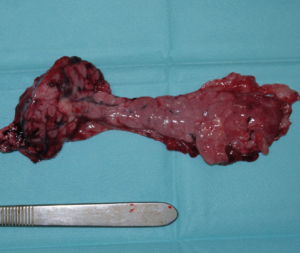

El tratamiento quirúrgico es el de elección para perros con enfermedad en estadio I (enfermedad localizada) o II (presencia de metástasis locorregional) e implica una pancreatectomía parcial para extirpar el tumor primario y cualquier metástasis visible (imágenes 4A-4K y 5A-5H). La mediana de supervivencia es más larga en los perros tratados quirúrgicamente en comparación con los perros tratados médicamente, como se describe en dos estudios donde la mediana del tiempo de supervivencia de los perros sometidos a pancreatectomía parcial fue de 381 días y 785 días, respectivamente, en comparación con 74 días y 196 días, respectivamente, en aquellos tratados solo con tratamiento médico.30 En otro estudio reciente, el tiempo medio de supervivencia registrado para 49 perros con insulinoma fue de 561 días y de hasta 746 días para perros que tuvieron resolución de hipoglucemia, con un tiempo medio euglucémico global (tiempos desde la cirugía hasta la primera detección de hipoglucemia en cualquier momento después de la cirugía) de 424 días para todos los perros.39

Imágenes 4A – 4K. Secuencia de imágenes quirúrgicas en un perro (con las imágenes del TC), durante una pancreatectomía total del lóbulo izquierdo y cuerpo del páncreas (usando la técnica de “guillotina” sutura/fractura con el nudo de Miller modificado) y resección de NNLL centinelas, por insulinoma en el cuerpo del páncreas.

Imágenes 5A – 5H. Secuencia de imágenes quirúrgicas en un perro (con las imágenes del TC), durante una pancreatectomía total del lóbulo derecho y parte del cuerpo del páncreas (usando la técnica de “guillotina” sutura/fractura con el nudo de Miller modificado) y resección de NNLL centinelas, por insulinoma en el lóbulo derecho del páncreas.

El tratamiento recomendado es la escisión quirúrgica. Aunque no suele ser curativa, los esfuerzos para extirpar todo el tumor primario macroscópico y la enfermedad metastásica reducirían la carga tumoral general. Esto, a su vez, puede ayudar a controlar la hipoglucemia, prolongar el tiempo libre de enfermedad y mejorar la supervivencia. El procedimiento quirúrgico consiste en una pancreatectomía parcial, eliminando todo el tejido neoplásico que pueda ser identificado (un 5 % corresponde a carcinoma de islotes difuso microscópico, detectable por palpación) junto con los NNLL centinelas +/- resección de nódulos hepáticos si estuvieran presentes.20 La hipoglucemia persistente tras la cirugía se ha considerado como factor negativo (signo de metástasis o resección incompleta).4